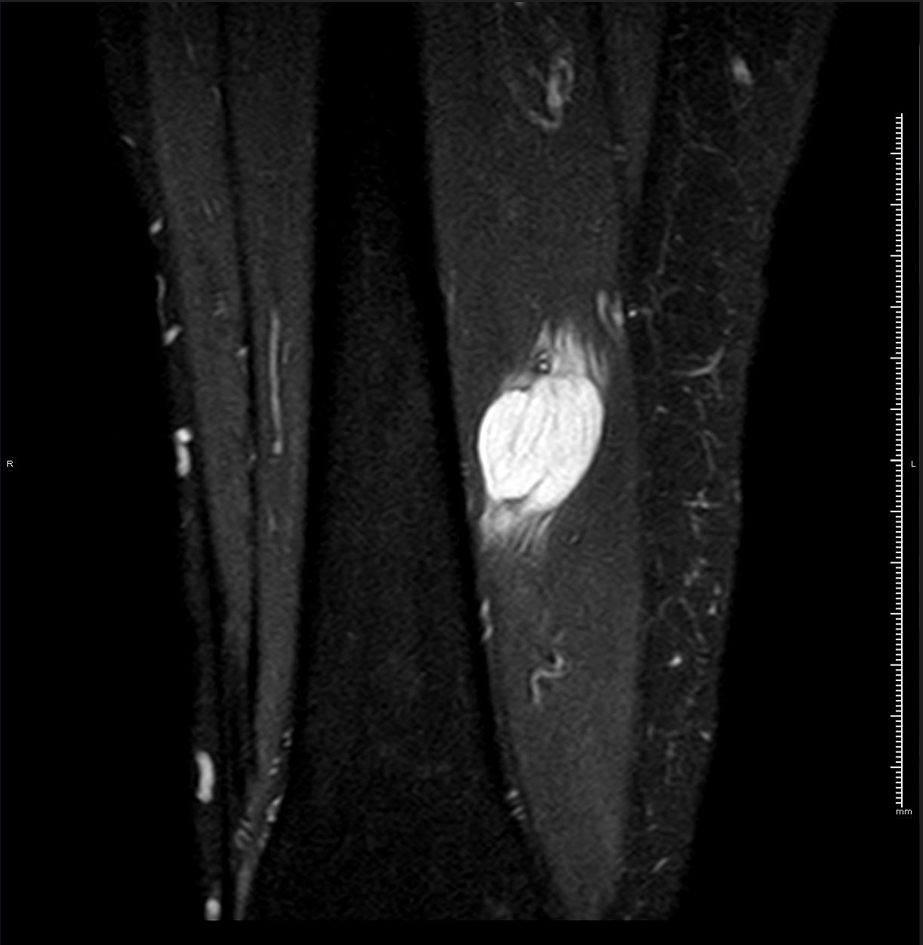

RM axial T1 con supresión grasa y gadolinio iv.

HALLAZGOS RADIOLÓGICOS